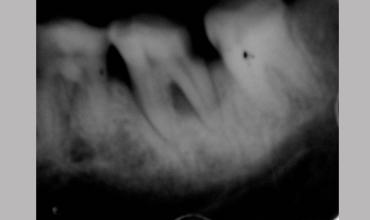

NON SURGICAL MANAGEMENT OF ENDODONTIC LESION AND SURGICAL MANAGEMENT OF PERIODONTIC LESION